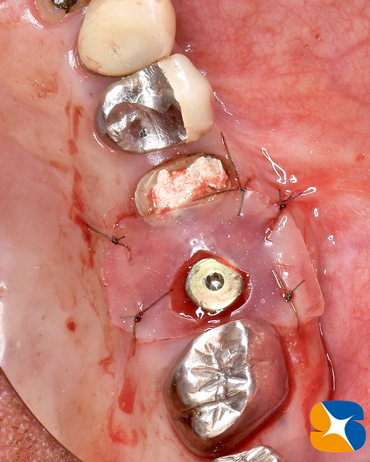

抜いた跡のところを一部削って、インプラントを移植しました。

※ノーベルバイオケア社製:アクティブ直径4.3㎜ × 深さ8.5㎜

移植されたインプラント周囲の骨を再生させるために、患者様の自己血を使ってコラーゲン(フィブリノーゲン)を製作する作業も並行して行います。

動物由来でない人工骨(β-tcp)とフィブリノーゲンを混ぜ合わせる直前の状態です。

人工骨とフィブリンが一塊となりましたので、骨の不足部に補填していきます。6ヶ月もすれば、本物の骨に置換されていく優れものです。

人工骨は、ソケットリフト(骨の厚みを6㎜→10㎜にボリュームアップ)にも活用しました。